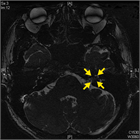

1. 急性感音難聴を来す疾患としては、本項で取り上げた突発性難聴、急性低音障害型感音難聴、外リンパ瘻の他にもメニエール病、音響外傷、ムンプス難聴などがある。『急性感音難聴診療の手引き 2018年版』ではこれらの疾患の診断の流れとしての診断フローチャートを示した。

1. 突発性難聴診断の推奨グレードA(1)またはB(2)は「発症した時期・状況につて把握する」(A)、「めまいの有無および症状の反復の有無について確認する」(A)、「両側同時に発症する突発性難聴は極めてまれであるため、他の原因による難聴について検討する」(A)、「聴神経腫瘍に伴う難聴との鑑別のため、MRIによる検査を行う」(B)、「再現性のある自覚的検査所見が得られない場合には、他覚的聴力検査を実施する」(B)、急性低音障害型感音難聴やメニエール病の鑑別では「低音部に限定した難聴かどうかを確認する(B)、メニエール病では発作を繰り返すことが特徴で割るため、経過を観察し再発の有無を確認する」(B)。